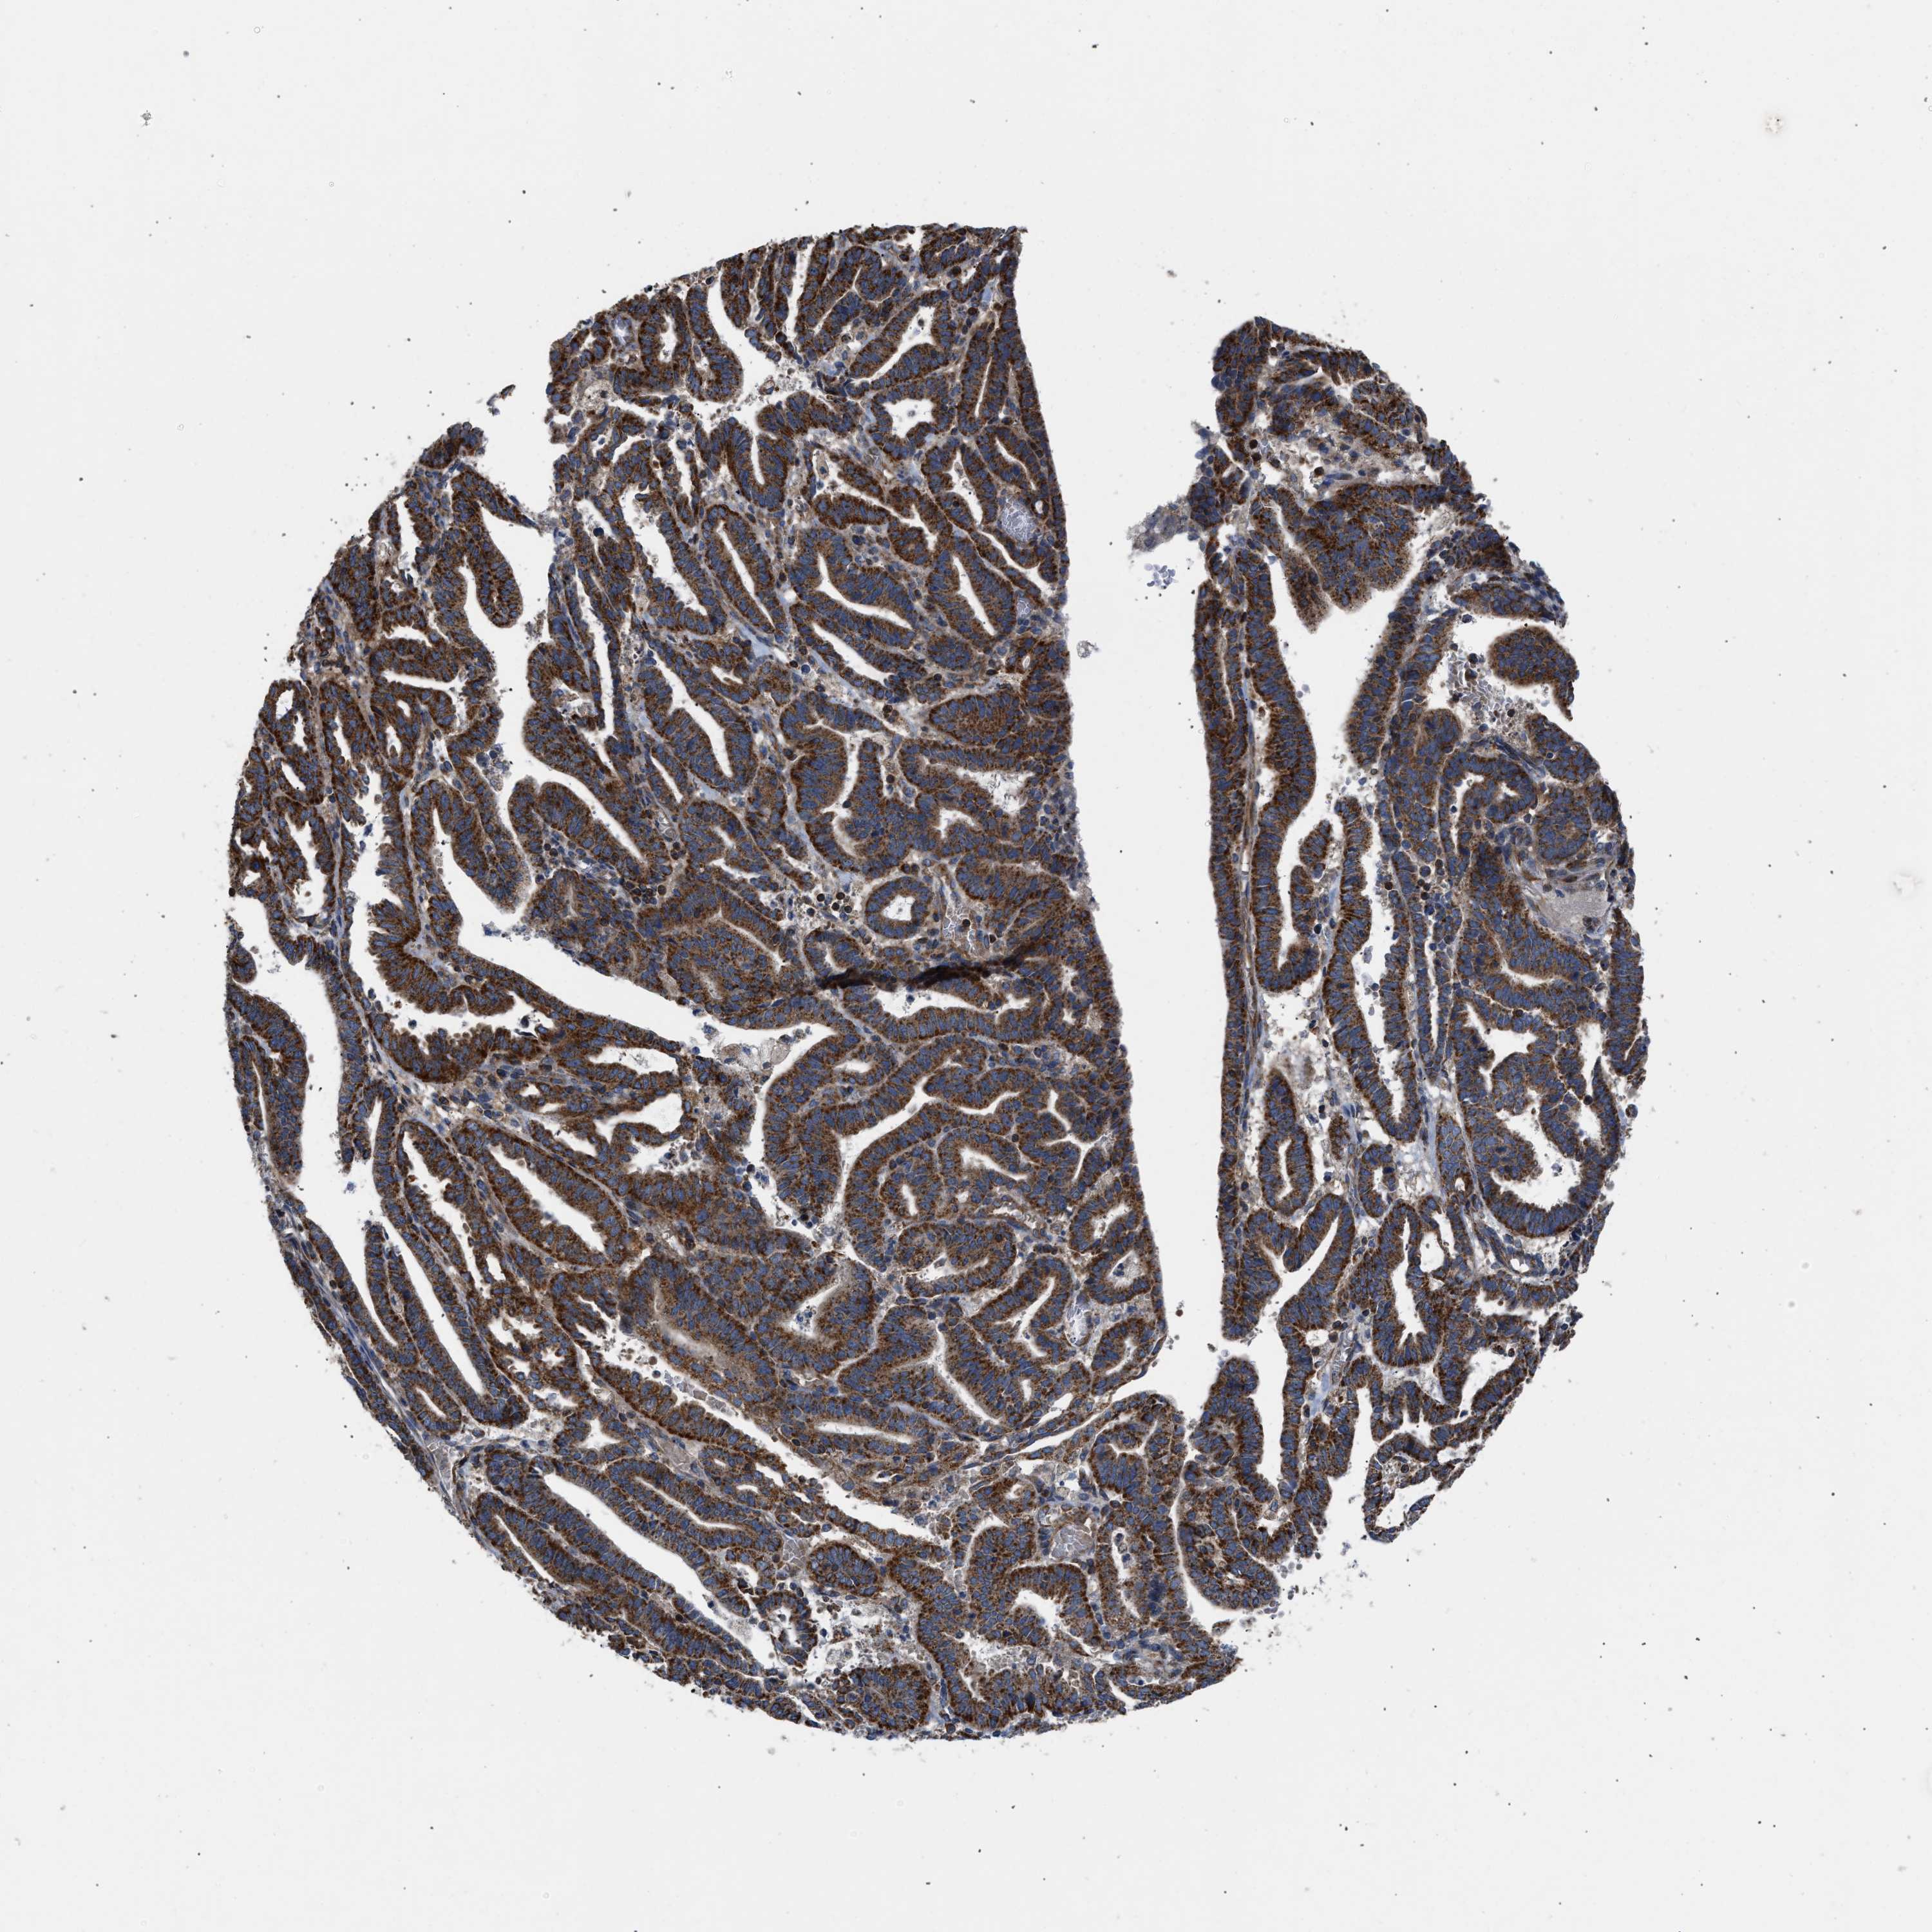

ENDOMETRIAL CANCER - Protein expressioni

A mouse-over function shows sample information and annotation data. Click on an image to view it in a full screen mode. Samples can be filtered based on level of antibody staining by selecting one or several of the following categories: high, medium, low and not detected. The assay and annotation is described here.

Note that samples used for immunohistochemistry by the Human Protein Atlas do not correspond to samples in the TCGA dataset.

Antibody stainingi

Antibody staining in the annotated cell types in the current human tissue is reported as not detected, low, medium, or high, based on conventional immunohistochemistry profiling in selected tissues. This score is based on the combination of the staining intensity and fraction of stained cells.

Each image is clickable and will lead to virtual microscopy that enables deeper exploration of all samples and also displays staining intensity scores, fraction scores and subcellular localization as well as patient and tissue information for each sample.

Antibody HPA003279

Antibody HPA003360

Antibody CAB019303